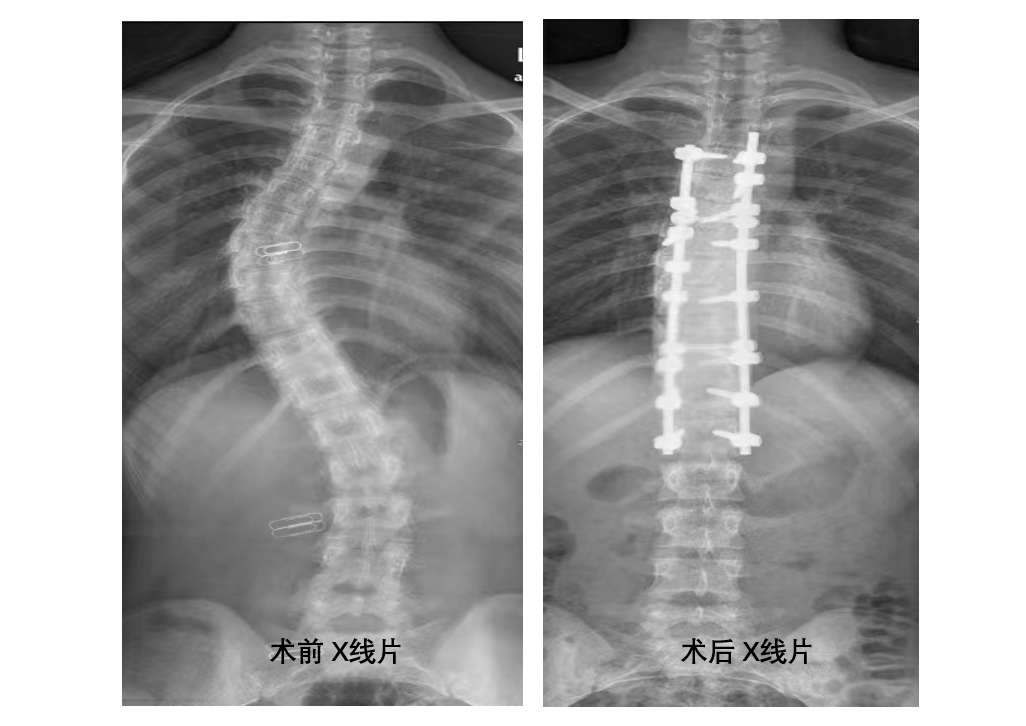

術(shù)前、術(shù)后x線片

“初見小萍是去年, 16歲的小姑娘雙肩明顯不平衡,X線片顯示脊柱側(cè)凸,主胸彎曲36°,雖然屬于典型的青少年型特發(fā)性脊柱側(cè)凸,但還未達到手術(shù)指征,我們建議她進行功能鍛煉,并觀察。沒想到,她的病情進展速度比較快,一年就長了十來度,必須要進行手術(shù)治療。”攀鋼總醫(yī)院骨科主任馬剛介紹說,脊柱側(cè)凸矯形手術(shù)是脊柱外科領(lǐng)域難度最大、風(fēng)險最高的手術(shù)之一,稍有不慎便會造成雙下肢截癱,大小便失禁。

小萍入院后,完善了相關(guān)檢查, X線片顯示主胸彎曲47°,且她的側(cè)凸分型為lenke 1BN型脊柱側(cè)彎。小萍胸椎椎弓根發(fā)育異常,加之骨骼基本發(fā)育完全,骨質(zhì)僵硬……都增加了手術(shù)的難度。 “ 要達到矯形目的,需要進行胸4~腰1長階段椎弓根螺釘固定,患者椎弓根發(fā)育較小,胸椎緊鄰胸主動脈和靜脈,椎管內(nèi)為胸脊髓,如果置釘出現(xiàn)問題,后果將難以想象。”“術(shù)前,我們必須根據(jù)CT影像規(guī)劃好植入螺釘?shù)闹睆礁嵌?,制定好旋棒的順? 術(shù)中,必須請麻醉科配合進行術(shù)中喚醒,同時準備好自體回收血。”…… 脊柱外科手術(shù)團隊反復(fù)研究病情, 多次進行術(shù)前討論、制定手術(shù)規(guī)劃。

充分的術(shù)前準備就緒,在麻醉科的大力支持和配合下,骨科脊柱外科手術(shù)團隊順利完成了后路減壓截骨矯形+椎弓根釘棒系統(tǒng)內(nèi)固定手術(shù),手術(shù)歷時 5  小時。術(shù)后復(fù)查X線片,側(cè)彎矯形成功。